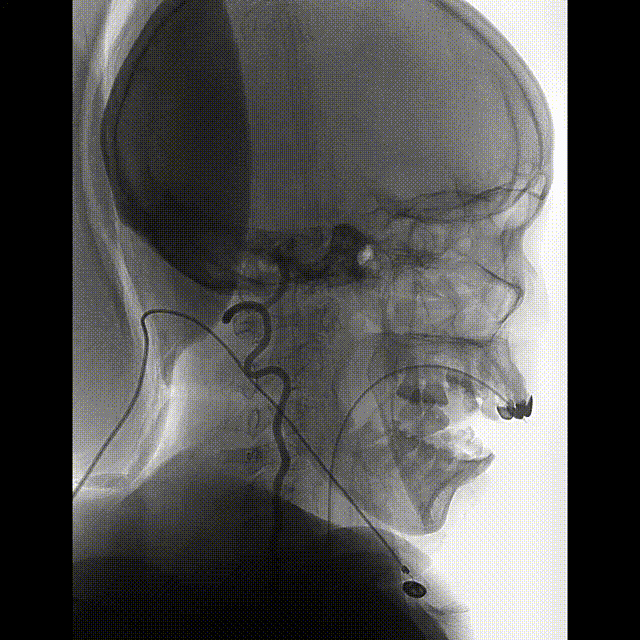

入院后立即行脑血管造影提示椎基底冗长扩张(基底动脉脑桥部分最宽处约5.2mm),伴有基底动脉多发动脉瘤,基底动脉尖动脉瘤(最大径约8mm)伴子囊和基底动脉下段动脉瘤(最大径约11mm)(图2)。

该患者在发病前并无症状,发表后为典型的动脉瘤性蛛网膜下腔出血的表现,剧烈头痛,CT平扫表现为广泛蛛网膜下腔出血和脑积水。CTA提示椎基底冗长扩张伴有动脉瘤。VBD患者伴有动脉瘤破裂常常分为两种,一种是囊状动脉瘤破裂,治疗方式与其他部位囊状破裂动脉瘤类似;另一种是梭形动脉瘤,大的梭形动脉瘤处理相对困难。有文献报道多个编织支架重叠的方法能够改善患者预后[8]。对于出现脑干压迫症状的患者血管内治疗效果欠佳,近一半的患者死亡[9]。此患者有两个动脉瘤,基底动脉尖动脉瘤更接近囊状动脉瘤,而基底动脉下段动脉瘤为大型梭形动脉瘤。对于基底动脉尖动脉瘤我们采取常规的动脉瘤栓塞策略,弹簧圈填塞集中在动脉瘤囊内,尤其是动脉瘤子囊的填塞。对于基底动脉下段动脉瘤我们采取大尺寸弹簧圈在梭形动脉瘤内均匀分布,使用大尺寸的LVIS支架尽可能使其与基底动脉能够较好贴壁从而能够促进血管壁的重建。对于弹簧圈结合支架治疗的方法有脑干穿支血管闭塞风险。近期有学者使用高分辨CTA对VBD患者进行分析,发现基底动脉扩张明显处的脑干穿支血管消失,而由其上、下方的血管通过软膜血管吻合提供代偿性血流[10]。因此在基底动脉明显扩张甚至形成梭形动脉瘤处使用弹簧圈疏松填塞是相对安全的,从此患者术后的神经功能以及CT和DWI结果得到了验证。此外进一步闭塞一侧椎动脉促使动脉瘤内血栓形成提高血管壁重建的可能[11]。